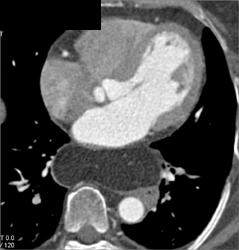

Normal Coronary Arteries